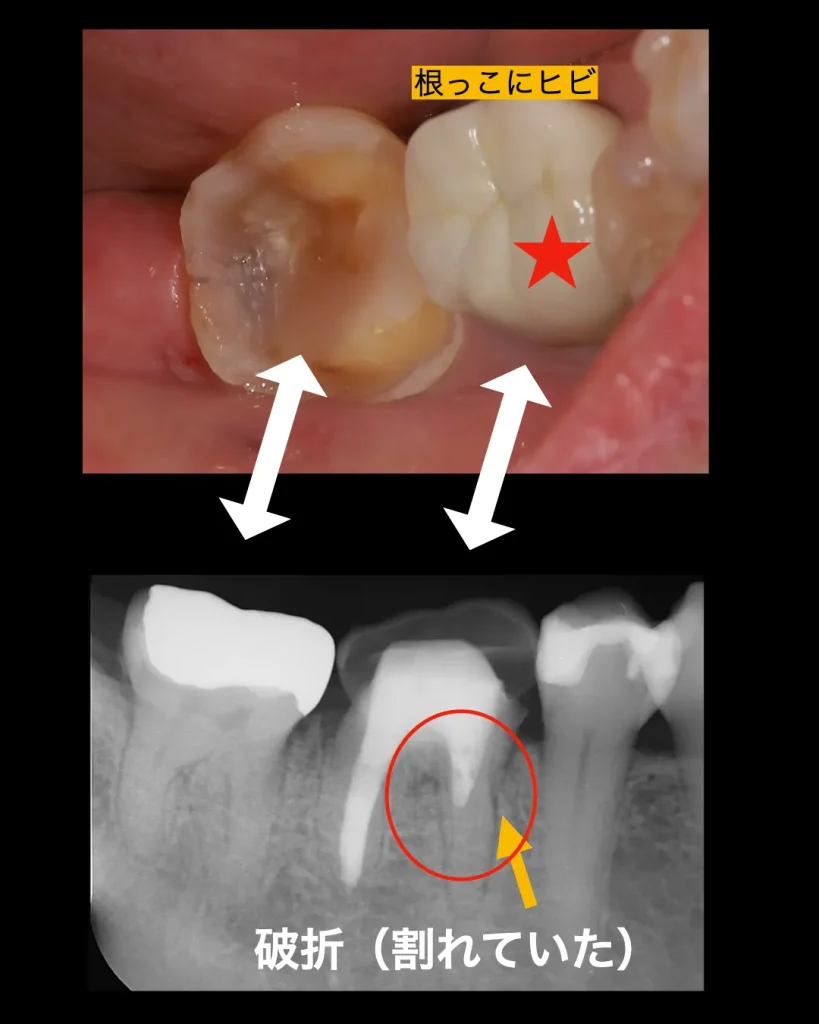

患者様は「噛むと痛みがあり、時に腫れることがある」との主訴で来院されました。

レントゲン検査の結果、6歳臼歯である第一大臼歯において、2本ある根のうち前方の根が歯根破折を起こし、周囲の骨が吸収している状態が確認されました。